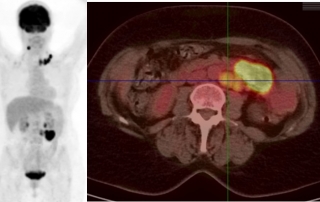

Biologie : hémogramme normal, augmentation des LDH à 680 UI pour une limite supérieure de la normale à 250 UI, sur la biopsie médullaire présence d’une infiltration par le lymphome à grandes cellules.

Classement : lymphome diffus à grandes cellules B CD20+ stade IV médullaire et péritoine, indice OMS = 0, LDH augmentées, IPIaa = 2.

Décision traitement initial par R-ACVBP x 4 cycles avec prophylaxie neuro-méningée et consolidation par méthotréxate à hautes doses x 2 cycles plus conditionnement autogreffe sous réserve d’obtention d’une rémission complète après R-ACVBP. En cas de réponse partielle, indication d’un contrôle histologique. En l’absence d’essai thérapeutique ouvert au moment du diagnostic, un traitement guidé par la TEP-FDG précoce après 2 cycles de R-ACVBP, n’est pas recommandé par la RCP.

Décision consolidation par méthotréxate et conditionnement BEAM autogreffe de CSH.

Evaluation réalisée 3 mois après autogreffe par scanner et TEP-FDG confirmait la rémission complète.